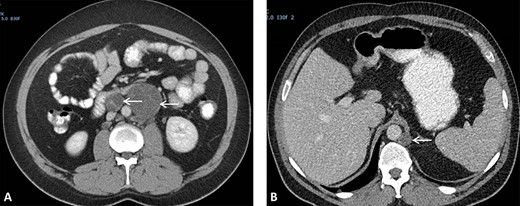

(A) CT scan showing two retroperitoneal masses. (B) CT scan showing retroperitoneal recurrence..

A 26-year-old man was first diagnosed in 2008 with a left-sided testicular tumor treated with inguinal orchiectomy. Resection specimen showed primarily embryonal cell carcinoma and teratoma. The patient, with stage IIC NSTGCT and intermediate-risk group according to International Germ Cell Cancer Collaborative Group [5], received four courses of cisplatin-based chemotherapy. Restaging procedures revealed normalized alpha-fetoprotein (AFP) and a normal beta-human chorionic gonadotropin < 1 U/L. Furthermore, CT scan of the thorax and abdomen showed a left-sided retroperitoneal para-aortic tumor mass, situated caudally of the renal hilus, measuring 6 × 7 cm (prior 5 × 5 cm), and a second retroperitoneal mass situated interaortocaval measuring 1.7 × 1.9 cm (prior 2.6 × 3 cm) (Fig. 2A). Subsequently, the patient underwent a midline laparotomy to resect these tumor masses. Surgical specimens consisted of R0 resection with fibrotic tissue and teratoma with mature and immature compounds. Due to a lack of patient adherence, follow-up protocol could not be executed.